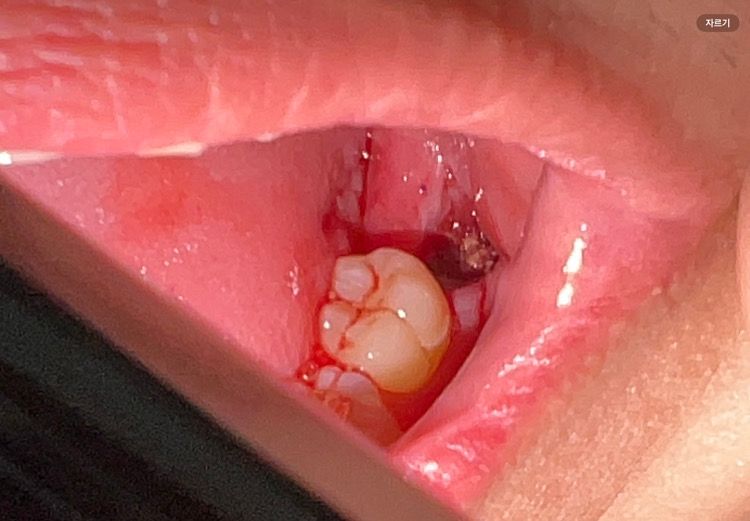

부분매복 사랑니 발치관련 질문있습니다

부분매복 사랑니 오늘 발치했는데요

1.저는 실로 꿰매지 않았는데 원래 그래도 되는건가요?

만약 문제가 있다면 어떤 조치를 해야하나요

2. 뽑힌 사랑니 자리에 피와같이 노란색 무언가가 있는에 이게 혈병인가요?

답변 해주시면 감사하겠습니다!

• 1번 째 사진

단순 발치의 경우는 봉합을 하지 않는경우도 잇긴합니다. 노란색은 염증이 염증이 피와 같이 나오는거 같습니다. 크게 문제가 잇어보이진 않습니다.

1. 출혈이 심하지 않으면 굳이 봉합하지 않기도 합니다.

2. 발치 후 치유를 위해 생기는 다양한 조직으로 보여집니다. 발치 후 주의사항 잘 지키시면 별 문제 없이 잇몸 나을겁니다.